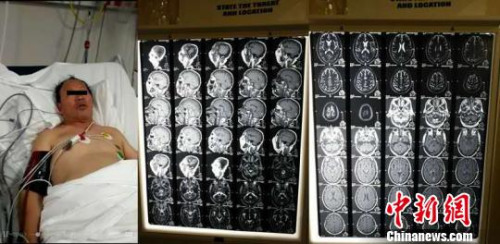

患者王某是中国派驻非洲的一位工程技术人员,20多年前从宝鸡去非洲技术援外,长期工作生活在伯茨瓦纳。入院前两周王某突发左侧肢体活动不能,言语含糊,意识不清,随后就诊于当地医院,被诊断为多发的小脑及大脑梗死,由于当地医疗条件十分有限,万分焦急的家属经多方打听,与西安交通大学第一附属医院血管外科教授刘建林取得了联系。

据介绍,刘建林教授随即通过网络进行了远程会诊,制定了有针对性的治疗方案。由于当地医疗技术水平有限,家属强烈要求回国治疗。考虑到患者病情尚不稳定,长时转运风险极高,刘建林教授与当地医护人员制定了详细的转运及治疗方案,以保障患者的生命平稳。

随后王某于12月3日乘坐国航班机抵达西安咸阳国际机场,并立即被救护车送往西安交大一附院。入院后,刘建林教授团队制定了详细的诊疗方案,通过介入手术打通重度狭窄的动脉,恢复脑血流。手术仅用时40分钟,即完全解除两根重要动脉的狭窄,而手术伤口仅3毫米。

术后,经过血管外科护理团队的精心护理及康复训练,患者恢复良好,出院时已能下床活动,正常交流,左侧肢体肌力由入院时的1级恢复到4级。